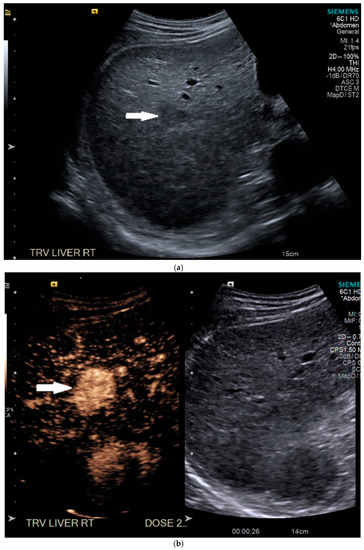

Routine US showed a heterogeneous, coarsened liver parenchyma with a suspected 2.2 cm hypoechoic structure in the right lobe on a background of geographic hepatic steatosis (Figure 1). Contrast was then administered intravenously with targeted imaging of the lesion to determine if it was focal fatty sparing or tumor. The lesion markedly enhanced (Supplementary Video S1) and began washout rapidly, and on delayed imaging, showed intense washout. It was deemed a LI-RADS M because of its early enhancement and for its marked washout (Figure 1). Given the LI-RADS M designation and for treatment planning, a four-phase CT was then approved by his health insurance company. Despite its size, the lesion was poorly visualized on the well-timed late arterial phase (Figure 2). It was equally subtle on the portal venous and 3 min phases. Knowing where the lesion was on CEUS allowed the radiologist to confirm the findings on CT, where it was deemed a LI-RADS 5 lesion. However, without the pre-existing knowledge of its presence in that location, the lesion was initially missed. The late arterial phase on the CT was bolus-triggered, which resulted in scanning occurring at 35 s post injection. Interestingly, on the CEUS, the lesion was already washing out and was iso-intense to liver by 35 s. This may explain why it was poorly seen on CT despite its intense, avid enhancement on US.

Figure 1.

Patient 1 ultrasound images, with liver lesion denoted by white arrow: (a) grayscale images showing the hypoechoic lesion. Post contrast administration ultrasound in arterial phase with matched low-mechanical-index B-mode grayscale on the right and subtraction-type post contrast images on the left (b) and delayed phase (c) of the lesion, which shows marked washout. Liver Reporting and Data System (LI-RADS M).